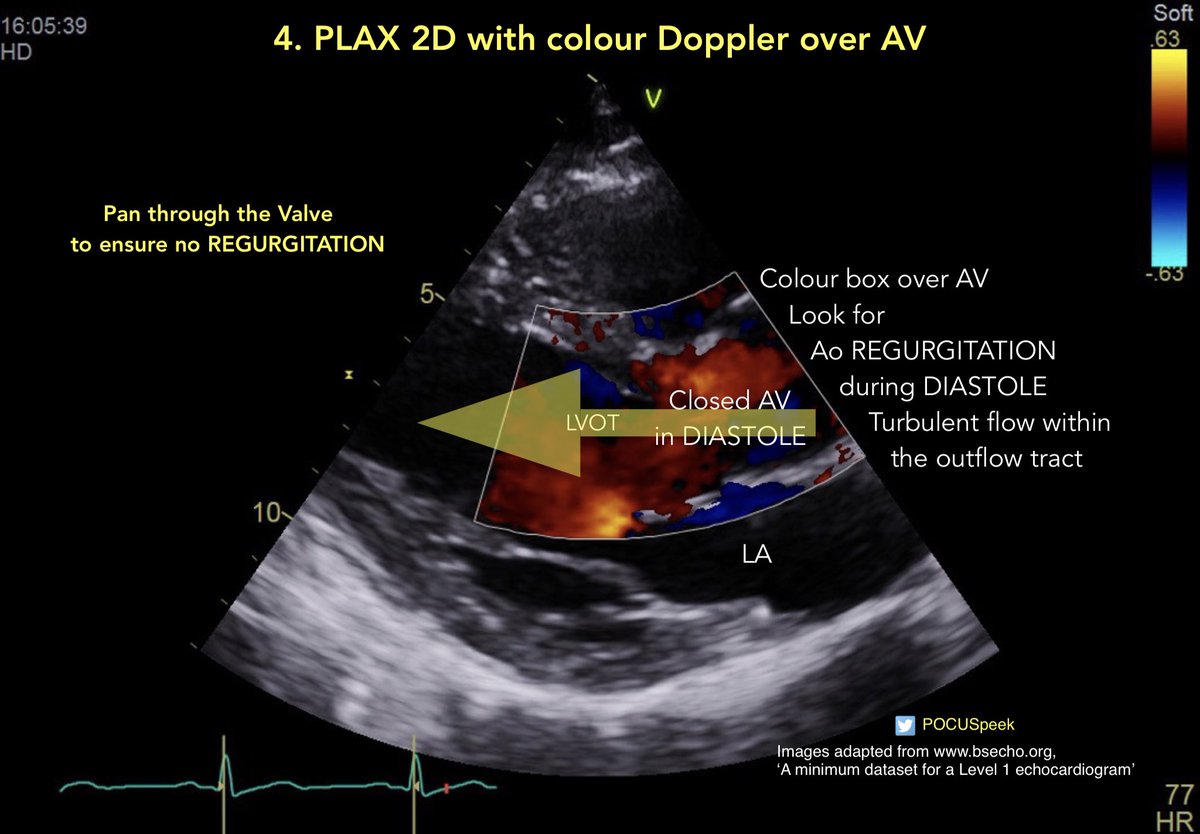

Aortic Regurgitation and Mitral Regurgitation Jet Direction 👇🏻 Jet Direction in PLAX 2D with Colour Doppler for #firstecho @pocusmeded @POCUS_Society @pocusfoamed @PracticalPOCUS @The_echo_lady @echocardiac

POCUSpeek's tweet image. Aortic Regurgitation and Mitral Regurgitation Jet Direction 👇🏻 Jet Direction in PLAX 2D with Colour Doppler for #firstecho @pocusmeded @POCUS_Society @pocusfoamed @PracticalPOCUS @The_echo_lady @echocardiac